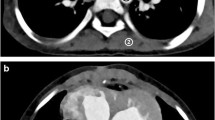

A 3-point scale was used to evaluate the presence of beam-hardening artifact from contrast-enhancement material: 3=no artifact, 2=mild artifact that still allowed evaluation of the (surrounding) anatomical structures, and 1=severe artifact that precluded evaluation. Representative images for three levels of beam-hardening artifact are shown in Fig. 1.

Representative axial contrast-enhanced CT images for the three levels of beam-hardening artifacts. a Score 3, no beam-hardening artifact, in a 1-month-old boy with single atrium, single ventricle, triscupid atresia and double-outlet of the right ventricle. b Score 2, mild artifact, defined as images that still allow evaluation of the surrounding anatomical structures. This image is in a 7-day-old boy with single atrium, single ventricle, pulmonary artery stenosis and total anomalous pulmonary venous return. c Score 1, severe artifacts that preclude evaluation, in a 10-day-old girl with atrial septal defects and ventricular septal defect